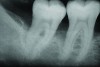

A series of full-mouth diagnostic radiographs that visualize each tooth or implant are critical as a baseline (Figure 11). The frequency and type of radiographs needed at maintenance depends on the severity of periodontal disease, as well as the extent of restorative treatment and caries susceptibility. With more advanced periodontal disease and restorative concerns, more frequent radiographs may be indicated. Vertical bitewing radiographs provide a better view of osseous crest levels and should be considered over horizontal bitewing radiographs for periodontal cases (Figure 12).

Fig 9. X-ray shows bone loss on the distal aspect and in the area of the furcation of tooth No. 31.

Figure 9

Fig 10. Postoperative x-ray depicts bone fill of the defect 2 years after regenerative therapy.

Figurer 10

Fig 12. Vertical bitewing radiographs.

Figure 12